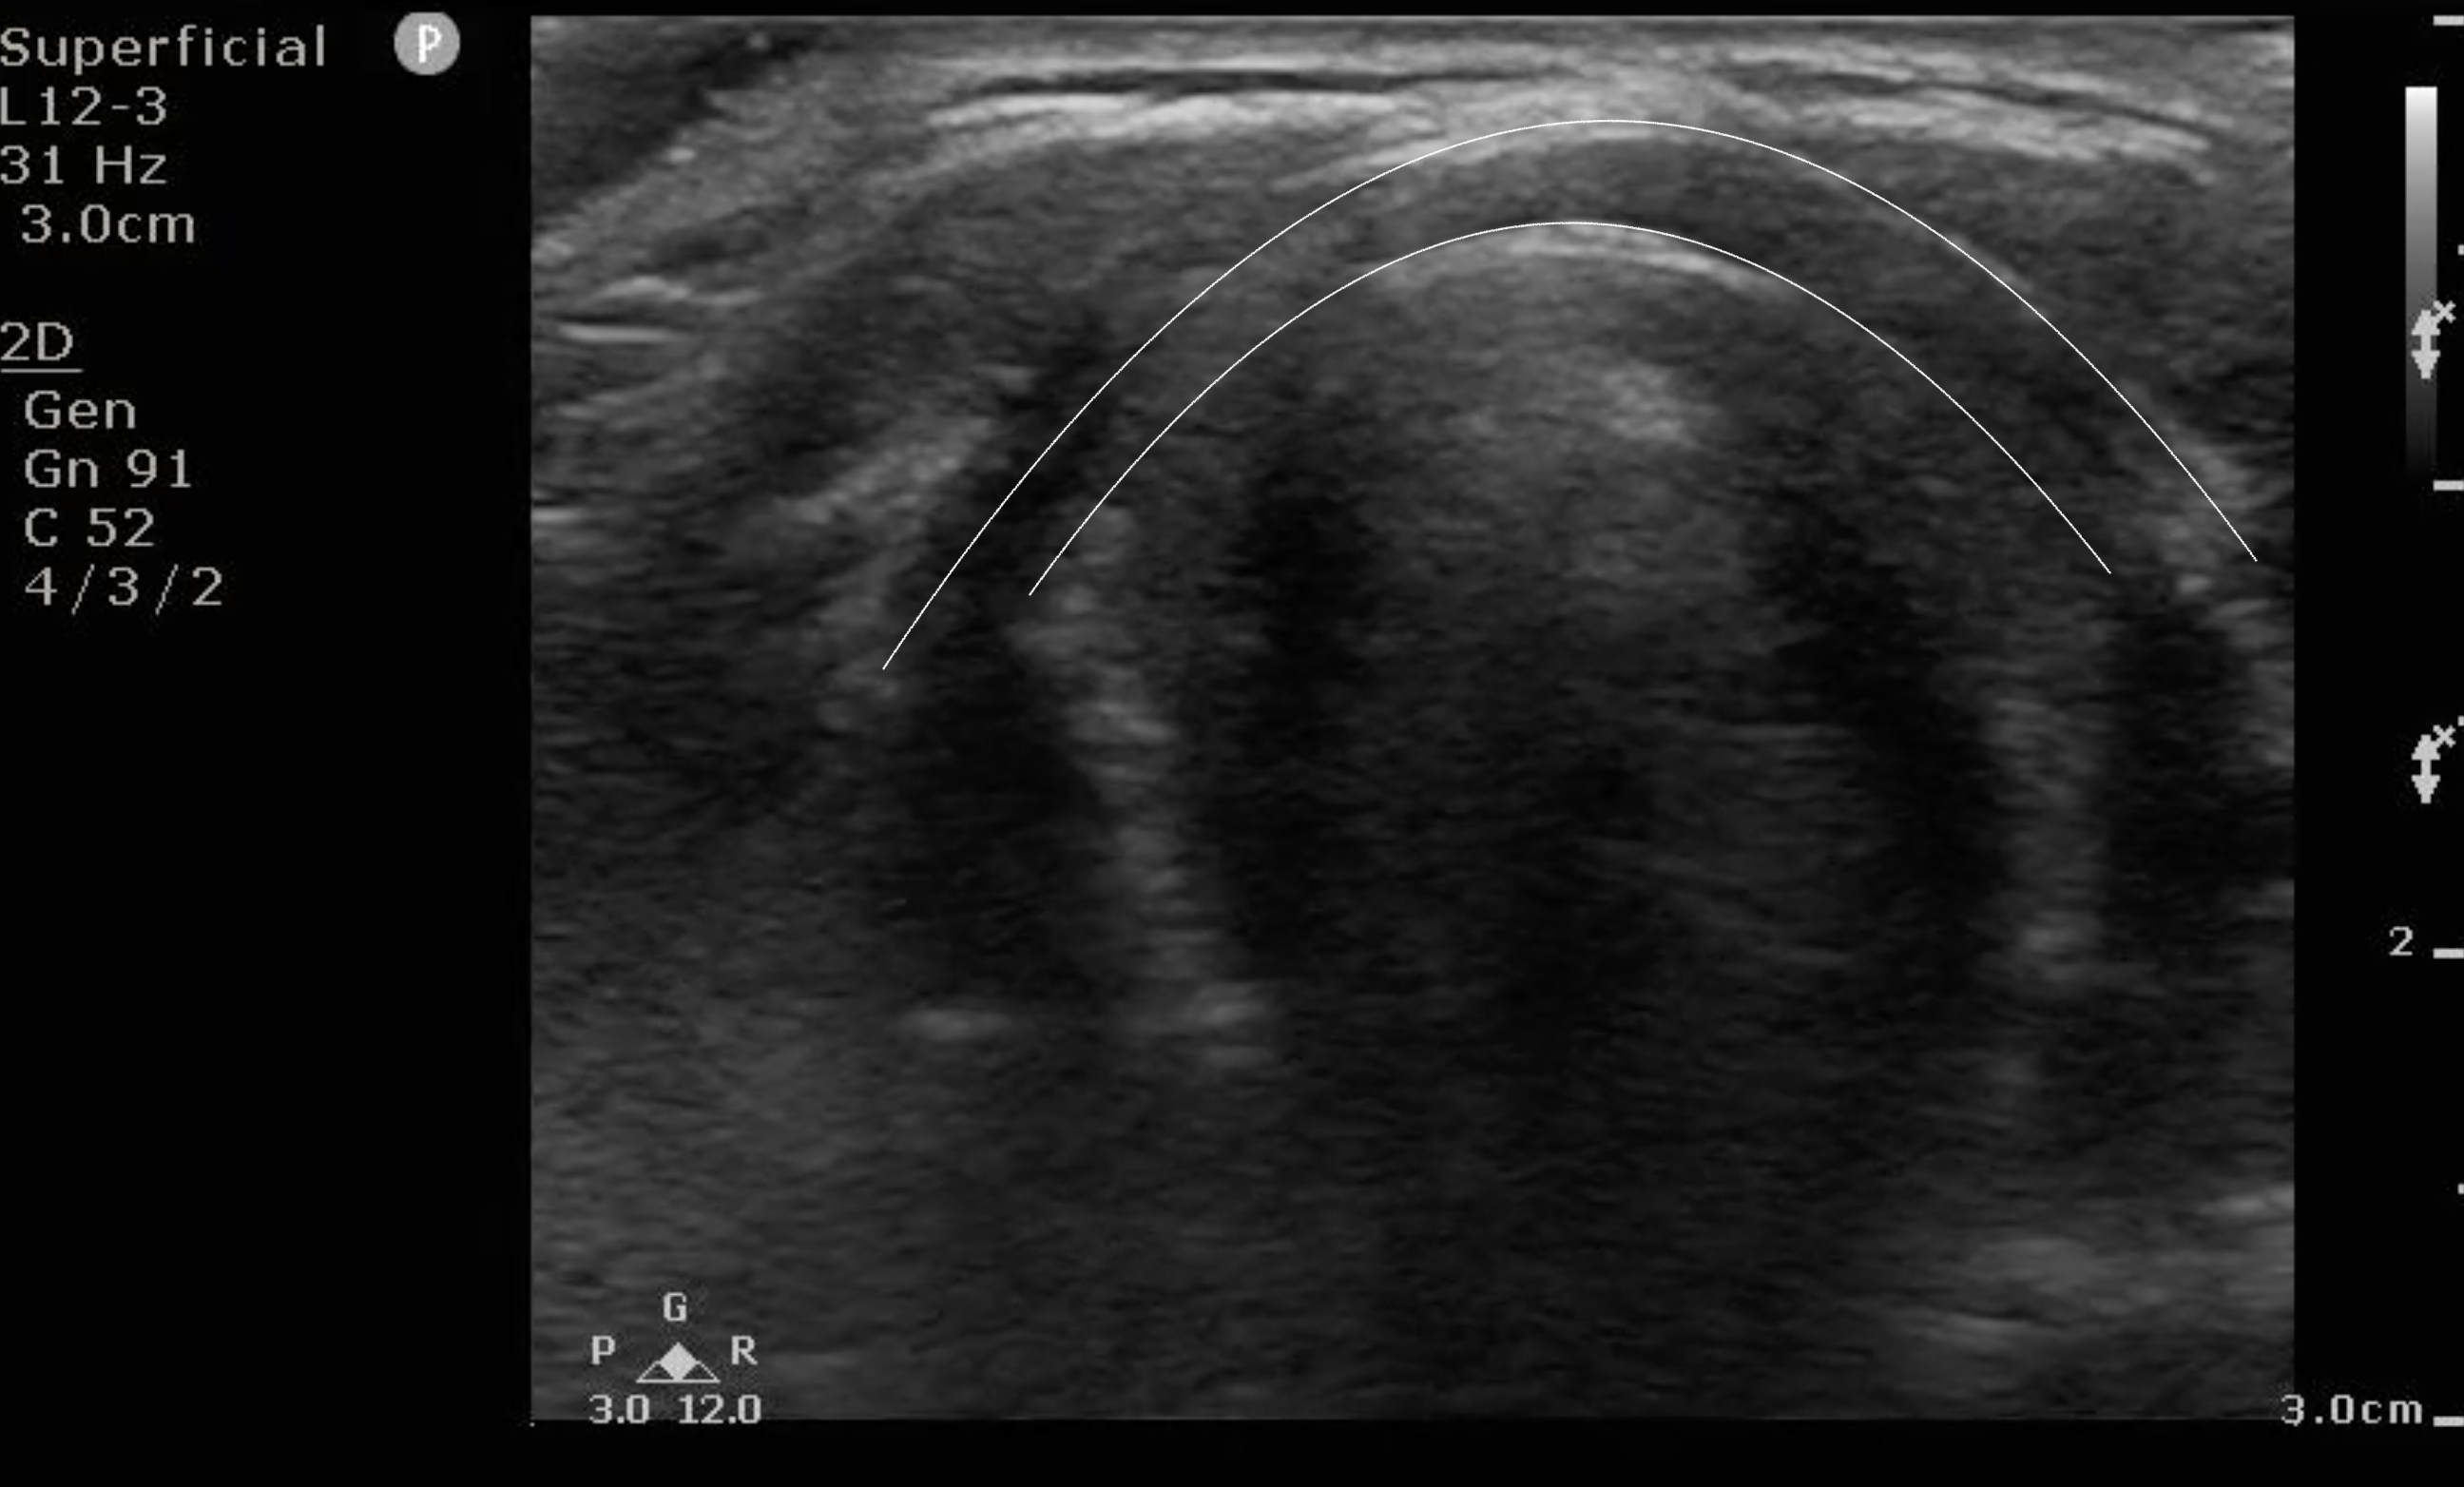

- Figure 6a and b. Step 6: As you slide down the patient’s neck, just after the cricothyroid membrane is the cricoid cartilage. It is a hypoechoic circular structure as noted in the figure between the two lines.